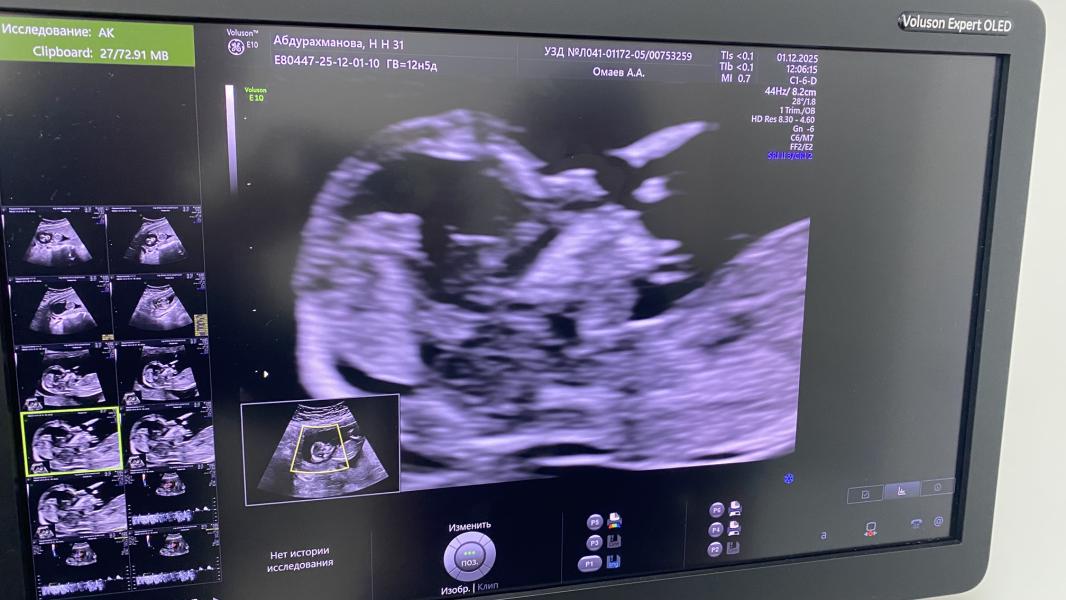

Спустя неделю, после скрининга у Эсетова я повторно сделала УЗИ в Хасавюрте у Амира Алиевича (13нед.), и он увидел носовую кость😍 сказал, что визуализируется, но на нижней границе нормы 2,0 мм

УЗИ на сроке 13 недель может быть уже не информативно.

У нас кость носа на 12.5 неделе была 1.9 мм